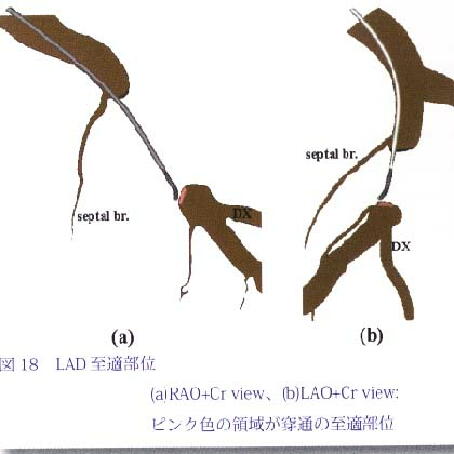

�摜17�F�K�C�h���C���[�͒��u�}�ɓ����Ă���DD1�Ɣ��Α���notch�����肻���D����